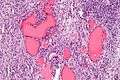

High mag.